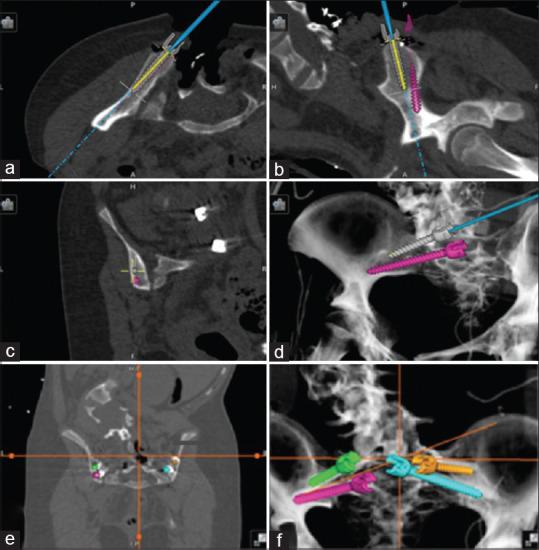

We report the use of computerized tomography (CT)-guided navigation for complex spinal deformity correction (anterior and posterior) in an 8-year-old patient with neurofibromatosis complicated by dystrophic pedicles, dural ectasia, and extensive vertebral scalloping. A retrospective review was conducted of the patient's medical records for the past 3 years, including the patient's office visit notes, operative reports, pre- and 2-year postoperative imaging studies. The patient successfully underwent anterior lumbar interbody fusion from L3-S1 using CT-guided navigation to negotiate the challenges posed by dural ectasia and vertebral body scalloping. One week after the anterior procedure, she underwent navigation-guided T10-to-pelvis posterior instrumented fusion. There were no perioperative or postoperative complications at 2 years. In patients with complex deformities of the spine, including dural ectasia, scalloped vertebral bodies, and decreased pedicle integrity, the use of intraoperative CT-guided navigation can benefit surgeons by facilitating the safe placement of interbody spacers and pedicle screws.

我们报告了在一名8岁神经纤维瘤病患者中使用计算机断层扫描(CT)引导导航进行复杂脊柱畸形矫正(前路和后路)的情况,该患者伴有营养不良性椎弓根、硬脊膜扩张和广泛的椎体扇贝样变。对该患者过去3年的病历进行了回顾性分析,包括患者的门诊记录、手术报告、术前和术后2年的影像学研究。患者成功接受了L3-S1前路腰椎椎间融合术,使用CT引导导航应对硬脊膜扩张和椎体扇贝样变带来的挑战。前路手术后一周,她接受了导航引导下的T10至骨盆后路器械融合术。2年时无围手术期或术后并发症。对于患有复杂脊柱畸形的患者,包括硬脊膜扩张、扇贝样椎体和椎弓根完整性降低,术中使用CT引导导航可通过促进椎间融合器和椎弓根螺钉的安全置入而使外科医生受益。